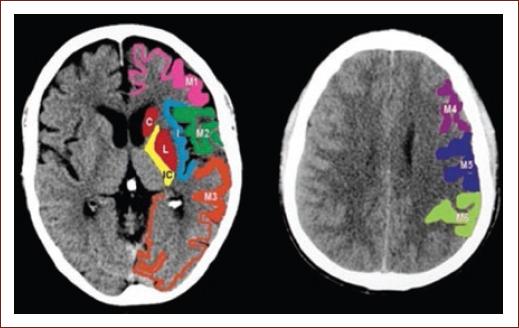

NCCT

Figure 2 Middle cerebral artery territories according to ASPECTS in a NCCT. Caudate nucleus (C), insular ribbon (I), posterior arm of the internal capsule (IC), lenticular nucleus (L), anterior MCA cortex (M1), MCA cortex lateral to the insular ribbon (M2), posterior MCA cortex (M3), superior-anterior MCA cortex (ACA-MCA watershed territory; M4), frontal posterior MCA cortex (M5), parietal cortex (M6). It is necessary to have at least one cut at the level of the basal ganglia and thalamus and another one just above the basal ganglia. ACA: anterior cerebral artery; ASPECTS: Alberta stroke program early CT score; MCA: middle cerebral artery; NCCT: non-contrast computed tomography.